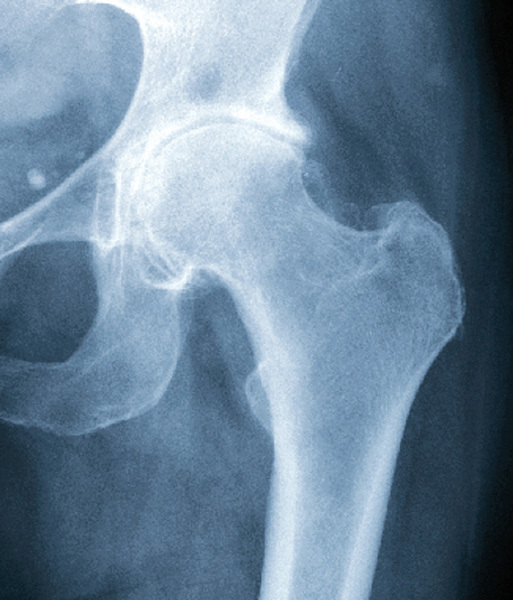

Coxarthrose

Radiographie d'une coxarthrose